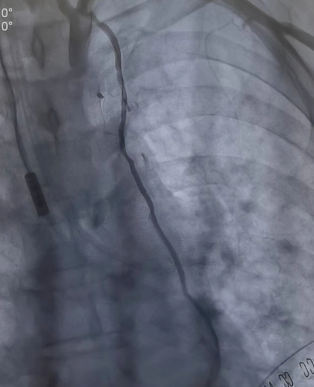

將兩者結(jié)合的手術(shù)方式就是雜交技術(shù)即“一站式微創(chuàng)”手術(shù)。手術(shù)先在左側(cè)胸壁做一個5-7厘米切口,進行左胸廓內(nèi)動脈-左前降支(LIMA-LDA)架橋。接著進行冠脈造影,檢查LIMA-LDA橋血管通暢度。同時在冠脈其他狹窄部位放入冠脈支架。

同期進行冠脈放支架(檢查LIMA橋血管通暢)